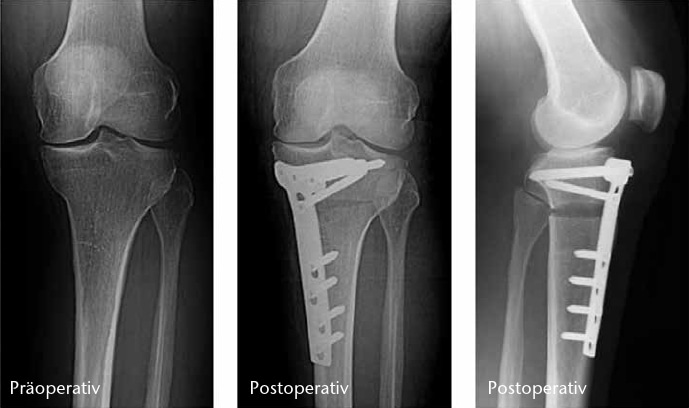

Umstellende Osteotomien am Knie haben zum Ziel, Achsdeformitäten zu korrigieren, um das degenerierte Kompartiment zu entlasten und die Lebensdauer des Gelenkes zu erhöhen 14. Sie eignen sich zur Behandlung von unikompartimentellen Varusoder Valgus-Gonarthrosen. Proximale Tibia-Osteotomien werden bei den weit häufigeren medialen Gonarthrosen bevorzugt, da sie biomechanisch Streckspalt- und Beugespaltweite korrigieren. Distale (suprakondyläre) Femur-Osteotomien verändern ausschließlich die Streckspaltweite und werden seltener bei lateraler Gonarthrose mit tibial physiologischem Varus durchgeführt. Durch die Einführung winkelstabiler Platten ist die öffnende hohe tibiale Osteotomie (HTO) bei Varus-Gonarthrosen erfolgreich etabliert. Sie ist gelenkflächenerhaltend, mit knorpelplastischen Maßnahmen kombinierbar, erfordert keine Knochenresektion und keine Fibula-Osteotomie. Die erhaltene laterale Knochenbrücke dient als Drehpunkt für eine stufenlose und biplanare Korrektur (M/L‑Kippung und A/P‑Neigung). Um einen paradoxen Effekt zu vermeiden, muss beim Aufklappen auch ein Innenband-Release erfolgen.

Osteotomien sind langfristig wirksam, um eine Endoprothese durchschnittlich 15 Jahre hinauszuzögern 15. Nach HTO kann eine spätere Endoprothesen-Implantation technisch anspruchsvoller sein. Ergebnisse bei Knie-Totalendoprothesen nach vorausgegangener Osteotomie zeigten jedoch keine negativen Effekte auf Standzeiten. Übergewichtige, Raucher und Frauen haben ein höheres Risiko des Therapieversagens. Die HTO eignet sich am besten für den normalgewichtigen aktiven Menschen, auch im hohen Alter und insbesondere als gelenkerhaltende Alternative zur Halbschlittenprothese (Abb. 4).